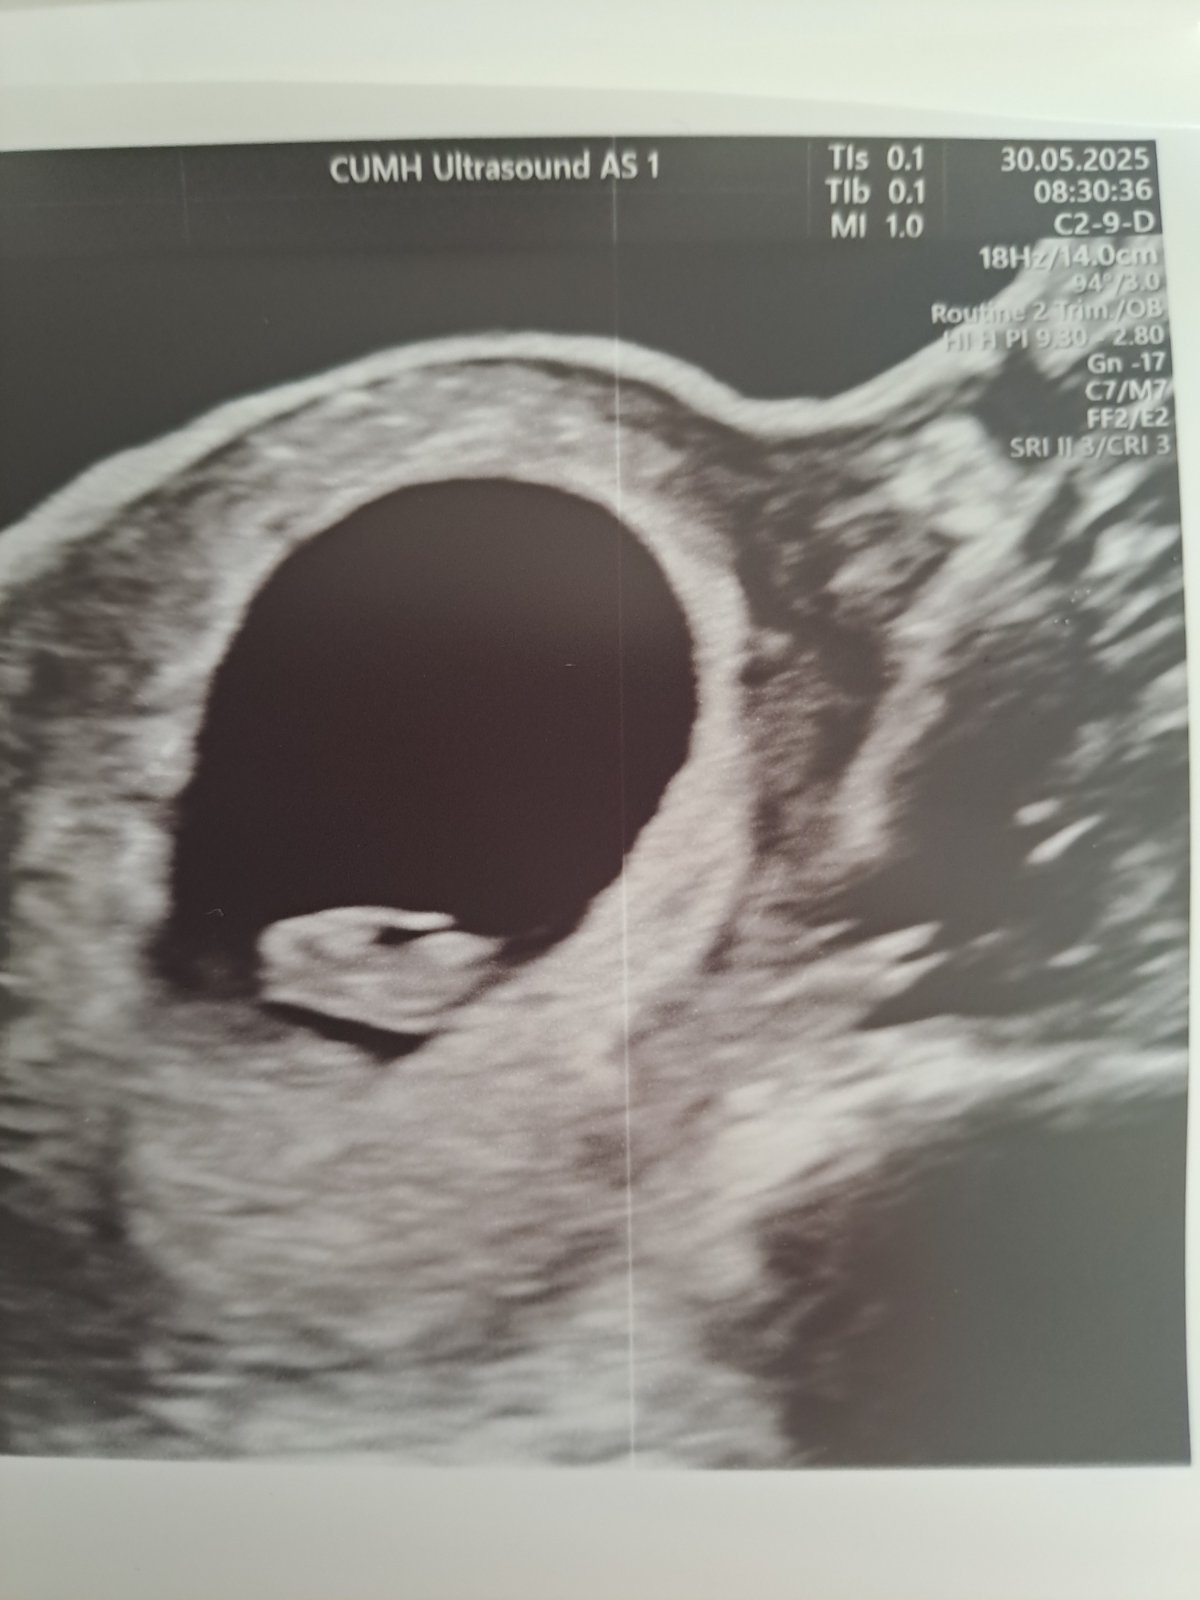

dnes jsem měla první ultrazvuk, který nebyl vaginální, ale přes břicho. Jsem ve 7+3 týdnu těhotenství. Velikost plodu odpovídá 7+4 týdnu a srdíčko bilo. Co mě ale zarazilo, bylo to, že nebyl vidět žloutkový váček.

Přijde Vám vše dle ultrazvukové fotografie v pořádku?

ano, je možné, že vaginálním ultrazvukem by vidět byl, protože vaginální sonda má vyšší rozlišení nebo jen Váš lékař nezachytil tu správnou rovinu řezu. Každopádně, pokud byl vidět plod odpovídající velikosti a tepající srdce, tak je vše naprosto v pořádku.